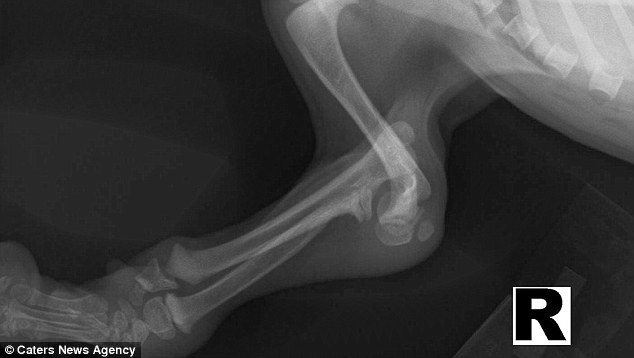

X光显示旺达腿部骨头完全错位。

旺达出生的时候,前肢几乎是完全弯曲的。

10个月大的旺达出生的时候,前腿和前爪几乎完全错位,独立行走对它而言无比艰难。